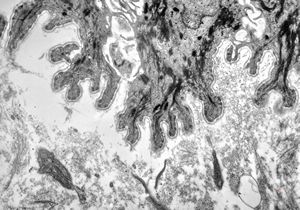

F, 1y. | epidermolysis bullosa … dystrophic form